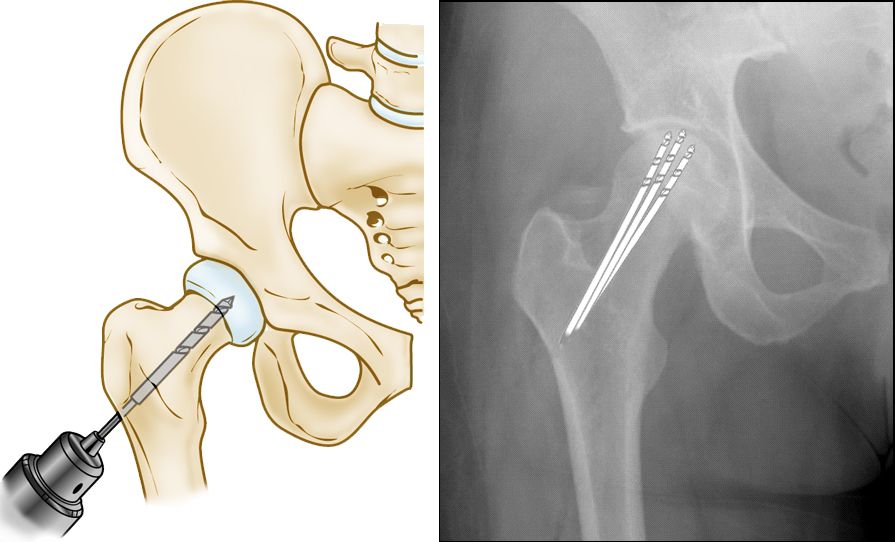

Core Decompression and Grafting

This procedure involves drilling one large hole or several smaller holes into the femoral head to relieve pressure in the bone and create channels for new blood vessels to nourish the affected areas of the hip.

When osteonecrosis of the hip is diagnosed early, core decompression is sometimes successful in preventing collapse of the femoral head and the development of arthritis.

Core decompression procedure

(Left) Illustration of core decompression. (Right) In this X-ray, the drill lines show the pathway of the small drill holes used in the procedure.

Core decompression is often combined with bone and cartilage grafting to help regenerate healthy bone and support cartilage at the hip joint. A bone graft is healthy bone tissue that is transplanted to an area of the body where it is needed. The tissue may be taken from a donor (allograft) or from another bone in your body (autograft).